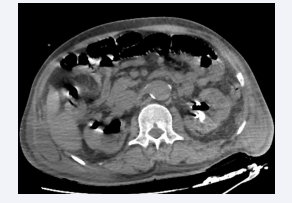

Figure 9 Axial section of an abdominal CT scan without intravenous  contrast injection showing an enlarged right kidney, with air bubbles  at the pyloric, intra-parenchymal, peri- and para-renal levels. The  appearance was consistent with Huang et al. class 3B left EPN.

Figure 9: Axial section of an abdominal CT scan without intravenous contrast injection showing an enlarged right kidney, with air bubbles at the pyloric, intra-parenchymal, peri- and para-renal levels. The appearance was consistent with Huang et al. class 3B left EPN.